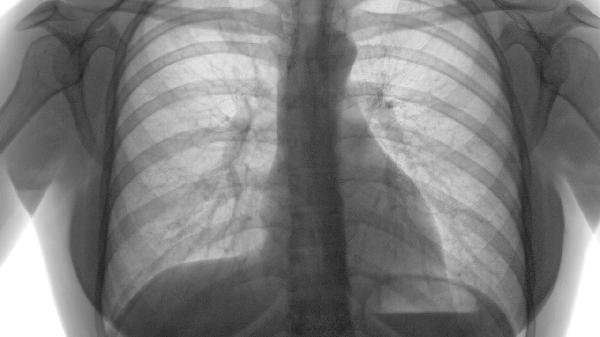

胸廓前后径增大呈桶状,肋间隙增宽,叩诊呈过清音。这是肺泡过度充气使胸廓持续处于吸气状态的表现,伴随呼吸时胸廓运动幅度减弱,听诊呼吸音普遍减弱。